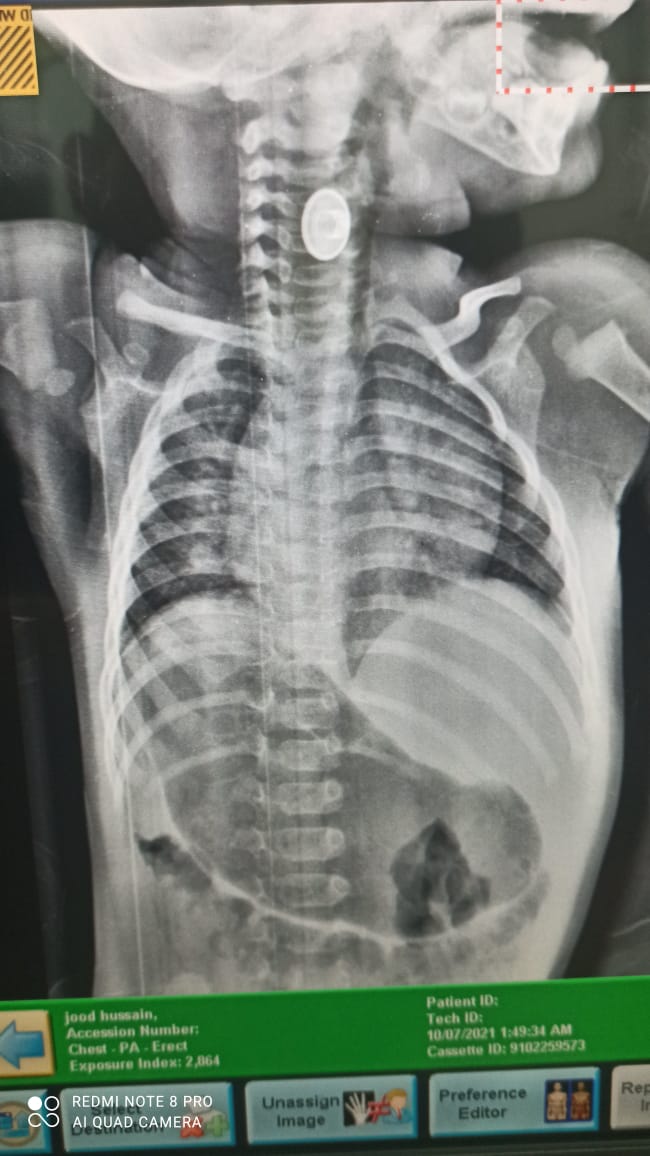

وأضاف التميمي، إنه "عقب إجراء الفحوصات اللازمة، وأشعة عادية على الصدر والمريء، حينها إتضح وجود جسم معدني عالق في المريء، وبجوار مجرى التنفس مباشرةً".